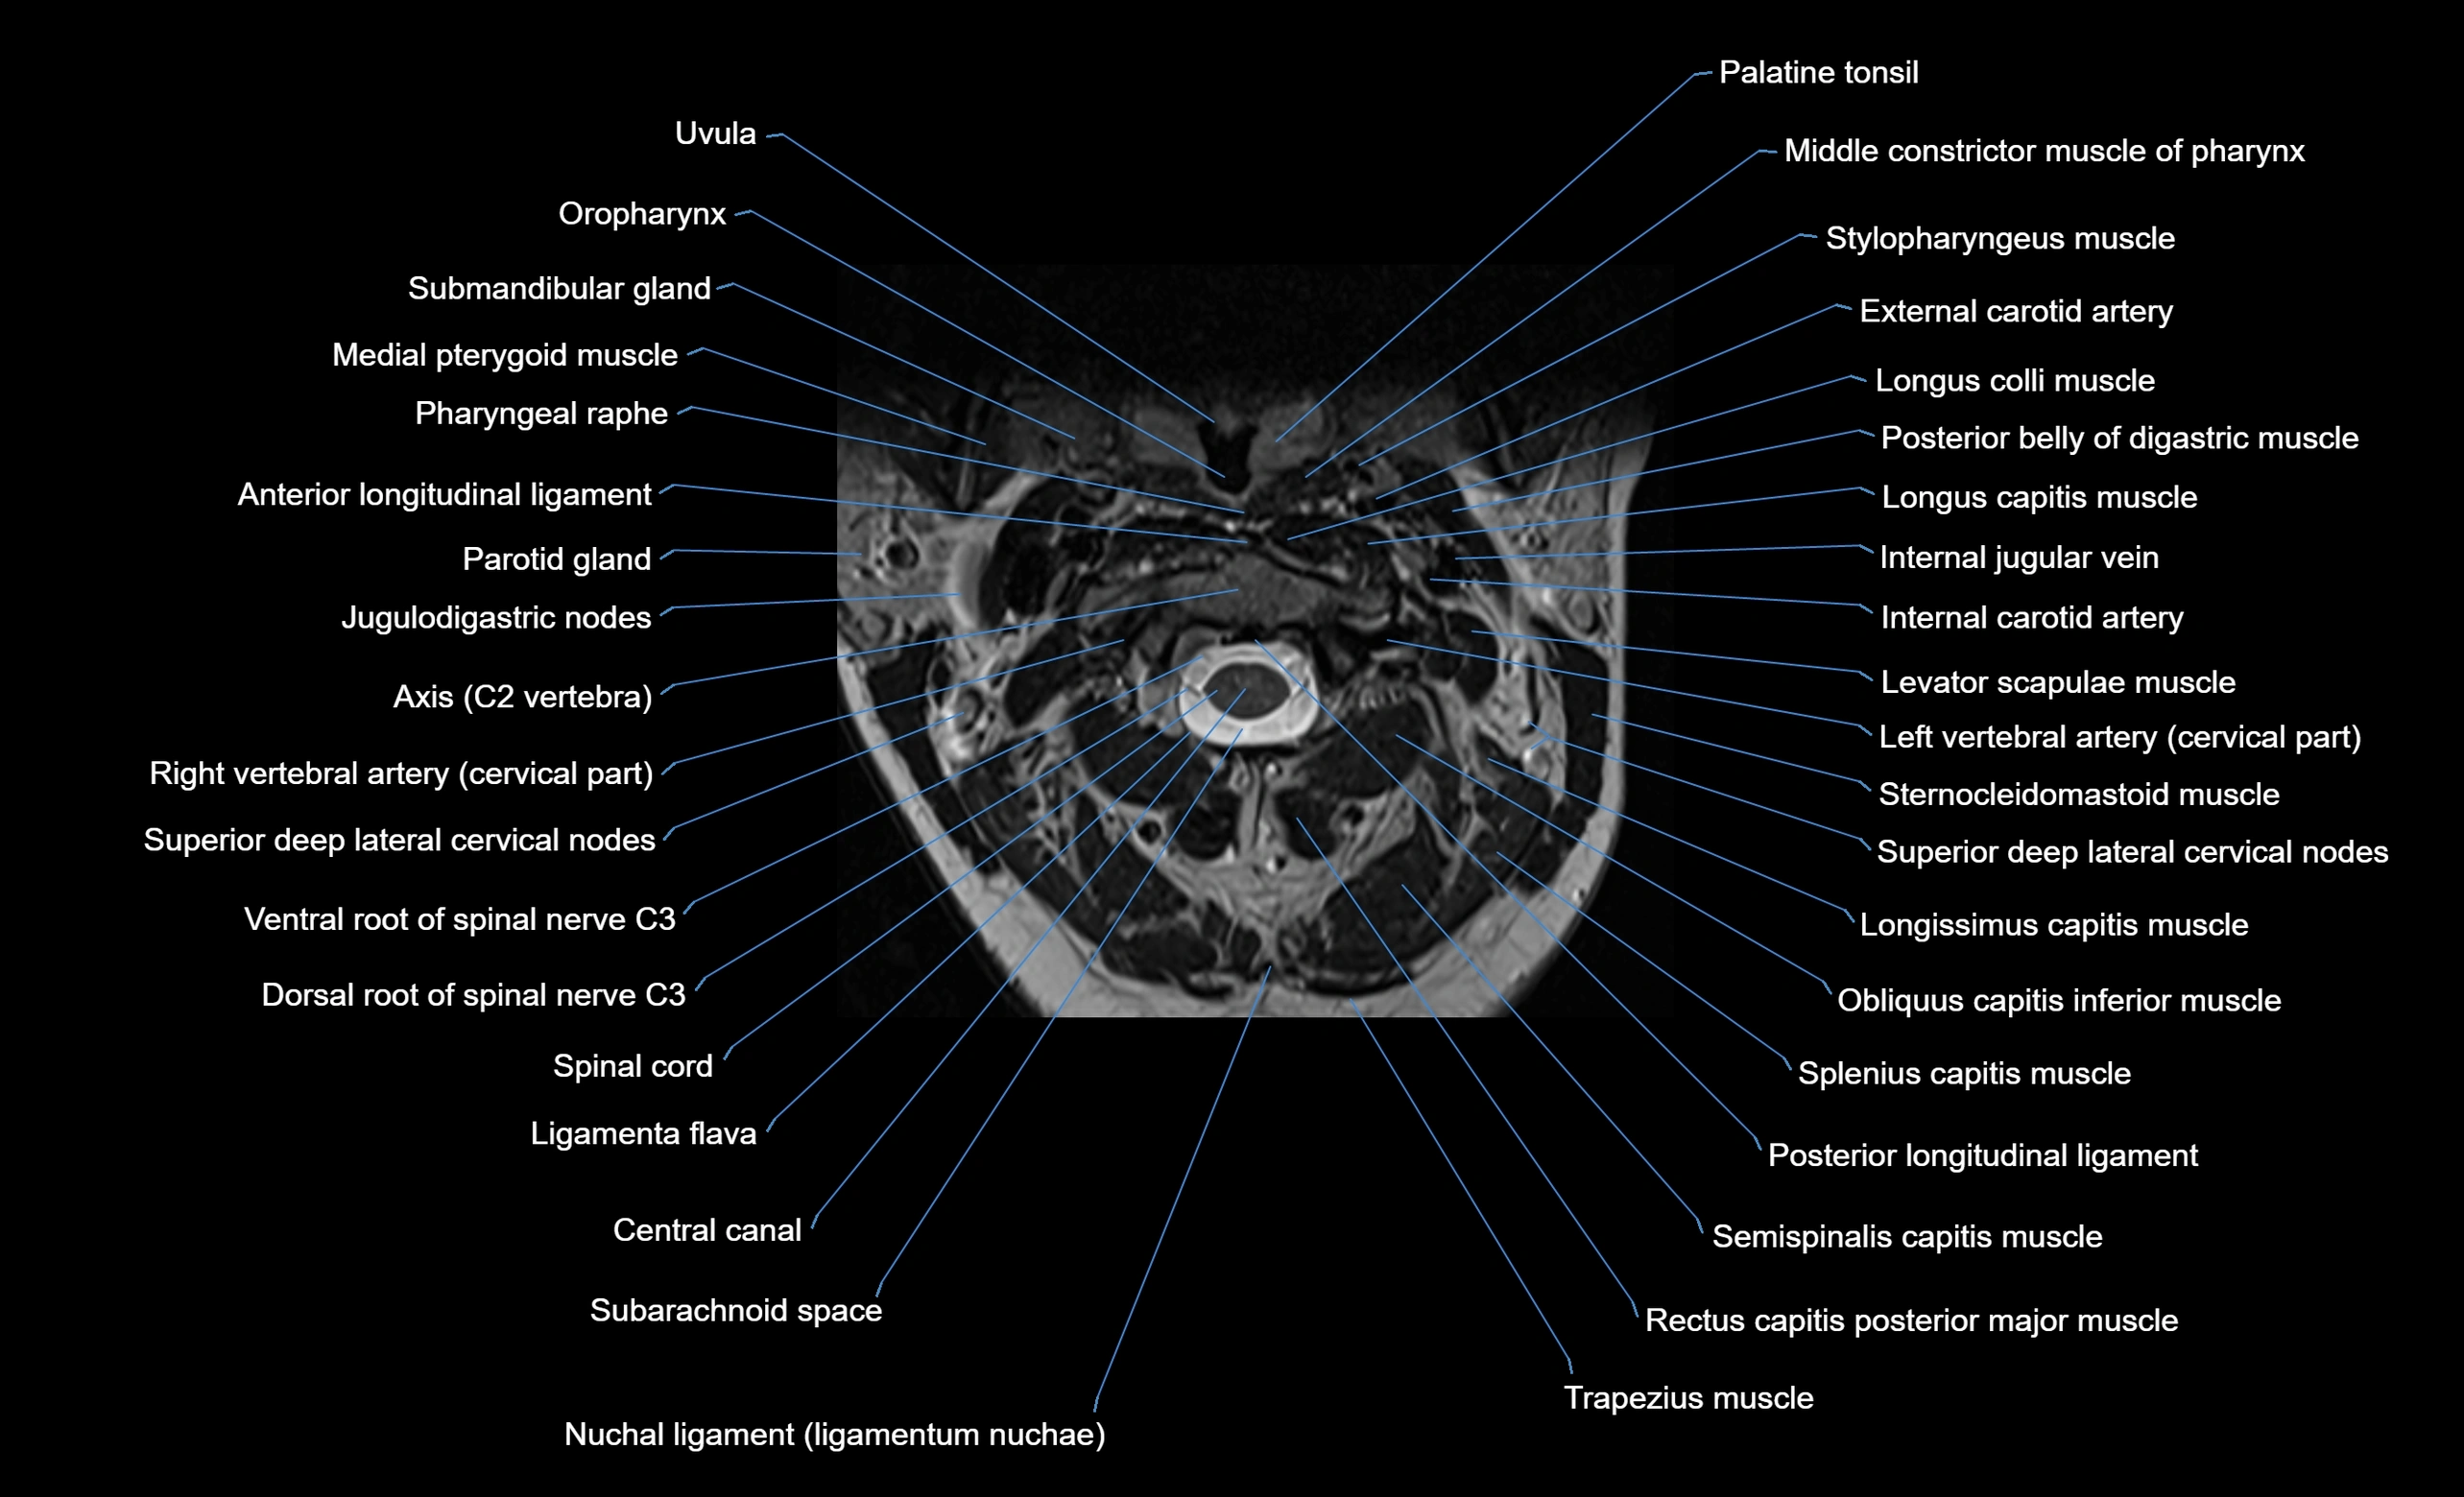

MRI appearance

T1-weighted images:

• Annular epiphysis: Low signal cortical rim at the vertebral margin

• Adjacent marrow: Intermediate-to-high signal in the vertebral body

• Disc interface: Clear delineation between bone and annulus

T2-weighted images:

• Annular epiphysis: Low signal intensity line

• Endplate cartilage (in younger patients): Intermediate signal

• Intervertebral disc: High signal nucleus pulposus

STIR:

• Annular epiphysis: Low signal cortical rim

• Adjacent marrow: Suppressed fat signal with preserved bony outline

• Utility: Highlights marrow and endplate interface in developing spine

MRI image

image